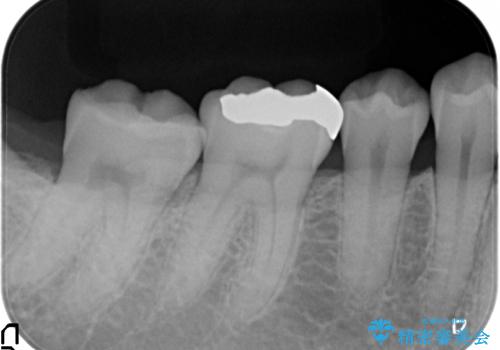

- 右下の銀歯を白くしたいといらっしゃった方の症例です。

銀歯を除去し、セラミックインレーによる修復を行いました。

当院のセラミックインレーはemaxという強度と審美性に優れた材料を使用しています。

またプレス方式でインレーを製作しているため、削り出しで製作するCADCAMより優れた適合性も持ち合わせており、虫歯が再発しにくい修復物です。